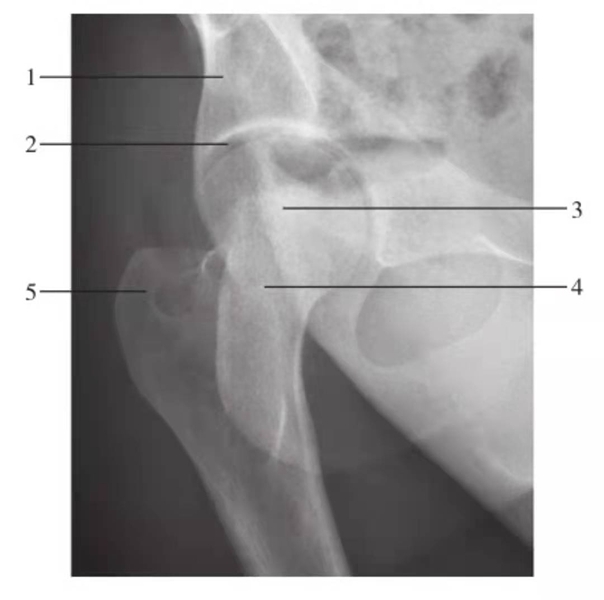

髋关节和股骨颈侧位

图3 髋关节和股骨颈侧位

1.髋臼;2.股骨头;3.股骨颈;4.大转子;5.小转子